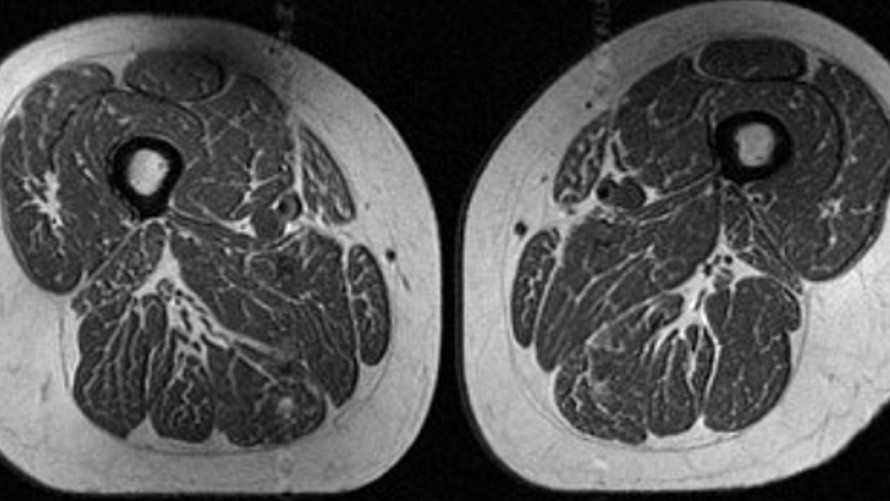

(Ngày Nay) - Hình ảnh trông giống như một lát thịt với những vân mỡ dày đặc, gợi liên tưởng đến một miếng bít tết thượng hạng với các dải mỡ đan xen. Tuy nhiên, đó lại là hình ảnh chụp cộng hưởng từ (MRI) đùi của một người phụ nữ 62 tuổi.

Ảnh chụp MRI vùng đùi của một phụ nữ với chế độ ăn có đến 87% là thực phẩm siêu chế biến.

Tiến sĩ Zehra Akkaya, nhà nghiên cứu và cố vấn tại Đại học California (San Francisco), cho biết: “Chế độ ăn của người phụ nữ này chủ yếu gồm ngũ cốc lạnh, kẹo socola, nước ngọt, hoặc các loại đồ uống đóng chai có đường”.

Tiến sĩ Akkaya là tác giả chính của nghiên cứu mới phân tích về tác động của thực phẩm siêu chế biến đối với mỡ trong cơ ở những người có nguy cơ bị thoái hóa khớp gối. Bà nhận định rằng những dải mỡ ẩn nấp giữa và bên trong các sợi cơ có thể là dấu hiệu của những vấn đề sức khỏe nghiêm trọng.

Một người phụ nữ khác tham gia nghiên cứu cũng có tình trạng vân mỡ trong cơ đùi, nhưng mức độ không nghiêm trọng bằng. Khoảng 29% chế độ ăn hàng năm của bà là thực phẩm siêu chế biến.

“Điều này đặc biệt đáng lo ngại bởi những cá nhân này dù tại thời điểm chụp MRI chưa có dấu hiệu thoái hóa khớp gối, nhưng chất lượng cơ bắp đã suy giảm rõ rệt”, Tiến sĩ Akkaya cho biết.

Kết quả cho thấy: Người phụ nữ có chế độ ăn chứa 29,5% thực phẩm siêu chế biến (BMI 32,6), nhưng mức độ vận động thấp hơn hẳn so với người phụ nữ có chế độ ăn chứa tới 87,1% thực phẩm siêu chế biến (BMI 31,8). Tuy nhiên, người phụ nữ nạp nhiều thực phẩm siêu chế biến hơn lại có lượng vân mỡ trong cơ đùi nhiều hơn một cách rõ rệt.